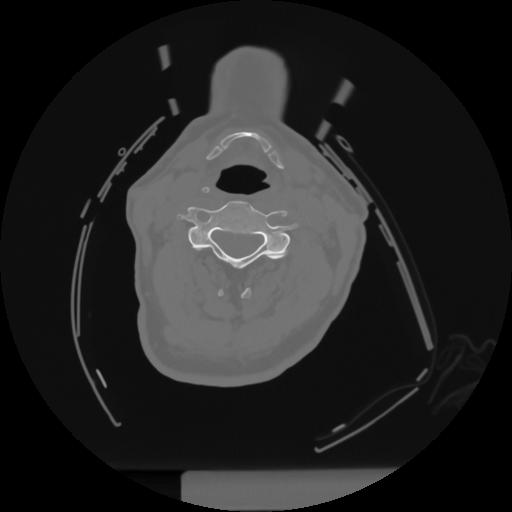

12 P.BLANDAS,,Vol,0.5,P.BLANDAS,,